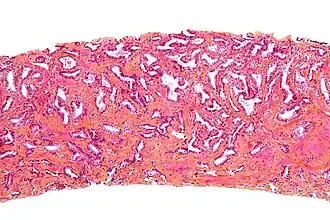

Micrografía de próstata que muestra una biopsia de próstata adenocarcinoma, el tipo acinar, el tipo más común de cáncer de próstata. | ||

La biopsia de próstata

La biopsia de los nódulos de las áreas sospechosas y de zonas al azar permite detectar el cáncer en sólo la mitad de los pacientes que presentan la próstata indurada. La biopsia también ayuda a determinar si el cáncer es o no multifocal. En más del 30% de los pacientes la biopsia con aguja no puede descubrir el cáncer, teniendo que recurrir a la repetición posterior de las biopsias.

Biopsia por punción con aguja hueca (core biopsia)

Es la técnica preferida (estándar) para diagnosticar un cáncer de próstata. Una biopsia es un procedimiento en el que se extrae una muestra de tejido y se examina al microscopio. La ecografía transrectal se utiliza para guiar e insertar una aguja fina y hueca a través de la pared del recto en algunas áreas de la glándula prostática. La aguja extrae un cilindro de tejido, normalmente de un centímetro de longitud y de 2 milímetros de ancho, que se envía a anatomía patológica para examinar si existe cáncer.

Las muestra de la biopsia se envían al laboratorio de anatomía patológica. El patólogo, un médico especialista en diagnosticar enfermedades en muestras de tejido, determinará si existe células cancerosas en la biopsia, examinándola al microscopio. Este análisis normalmente tarda de uno a tres días. Si existe cáncer, el patólogo también asigna un grado (puntuación Gleason).